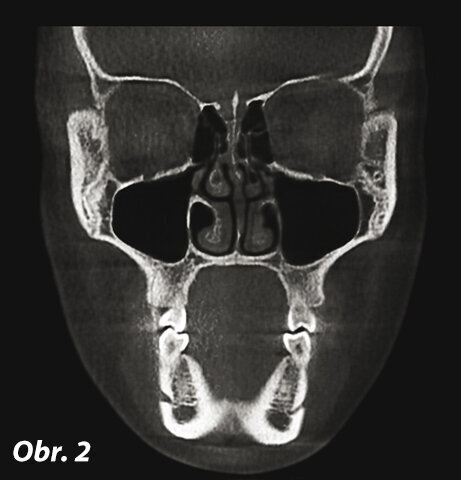

Koronální rovina (obr. 1, 2)

Koronální rovina je umístěna ve frontální části obličeje, probíhá víceméně rovnoběžně s vestibulárním povrchem předních zubů. Rozděluje lebku na dvě části: anteriorní a posteriorní. Struktury mohou být prohlíženy směrem dopředu nebo dozadu.